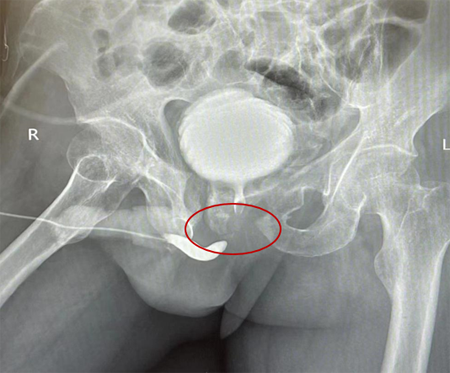

尿道造影显示尿道完全断裂

6个月过去了,老张的儿子带着他再次来到了医院,他们这次是来修补尿道的,了解到北京积水潭医院已派驻泌尿外科专家翟建坡到贵州工作,老张更是对自己的手术信心满满。翟建坡主任查看老张的复查结果后表示:老张骨盆骨折导致后尿道断裂,后尿道已完全闭锁,尿道断裂闭锁的长度较长(约2.5-3cm),需要行后尿道切除吻合术。